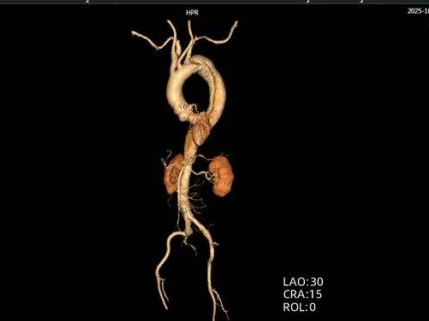

时间就是生命。医生会结合症状,快速进行以下检查:医院会根据CT血管成像(CTA)进行诊断。如确诊为主动脉夹层,则会进行紧急处理,立即镇痛、控制血压和心率(如静脉注射β受体阻滞剂)。

主动脉腔内修复术:微创治疗。通过大腿根部的股动脉,将一个覆膜支架送入主动脉夹层部位,像打补丁一样覆盖住内膜破口,使血流不再进入假腔,促进假腔血栓化愈合。